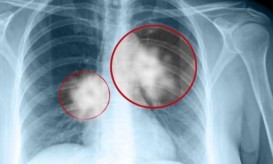

Ο προσυμπτωματικός έλεγχος για τον πνεύμονα γίνεται με αξονική τομογραφία θώρακος χαμηλής δόσης.